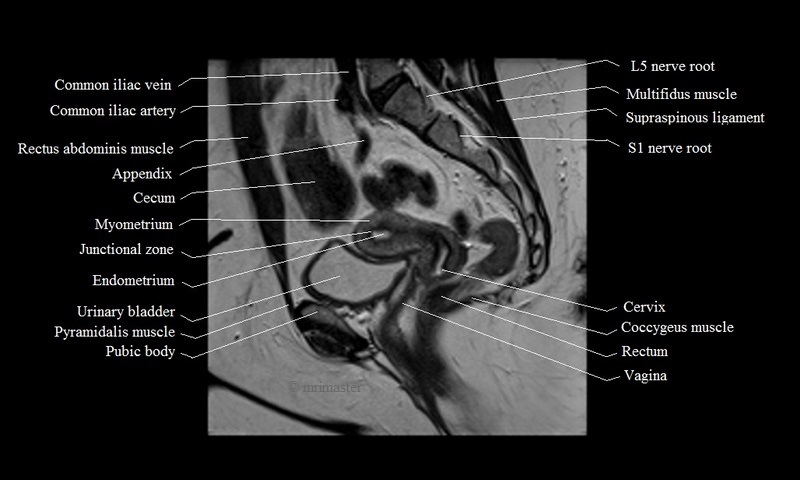

Go over this normal MRI of the female pelvis